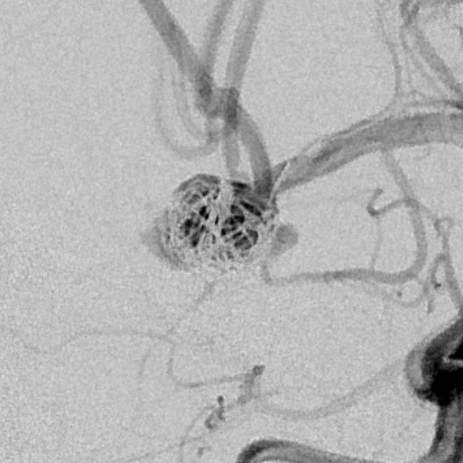

粗大分支从破裂瘤体上发出来,急性期能单纯致密栓塞吗?

病史:中年女性,新冠感染,颅内动脉瘤破裂,Hunt-Hess 4级